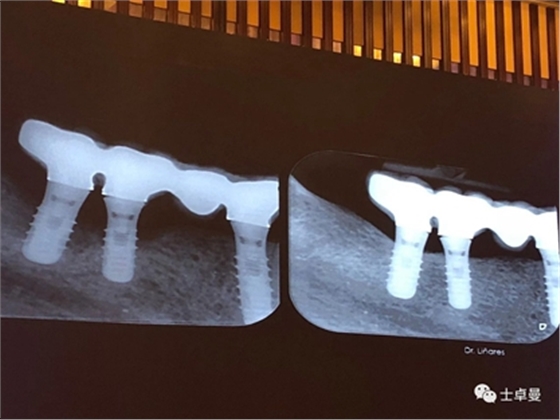

4、種植體周圍炎的治療

接下來Dr. Laurence Adriaens介紹了種植體周圍炎的治療,即非手術(shù)方式治療和手術(shù)方式治療。非手術(shù)方式治療提倡對患者進行有效的口腔衛(wèi)生指導(dǎo),患者必須掌握有效的菌斑控制方法,以保持良好的口腔衛(wèi)生,還可以選用種植體專用的牙線清潔義齒鄰面及其周圍軟組織。同時應(yīng)養(yǎng)成每半年到一年定期復(fù)查,進行專業(yè)清潔的習(xí)慣。

手術(shù)方式治療則需通過翻瓣清潔種植體及修復(fù)體上菌斑牙石,推薦在此過程中使用士卓曼鈦刷,因為該鈦刷不會損傷種植體表面細微結(jié)構(gòu)。之后進行植骨蓋膜來促進種植體周圍吸收部分的骨的重建。